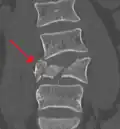

A burst fracture is a type of traumatic spinal injury in which a vertebra breaks from a high-energy axial load (e.g., traffic collisions or falls from a great height or high speed, and some kinds of seizures), with shards of vertebra penetrating surrounding tissues and sometimes the spinal canal.[1] The burst fracture is categorized by the "severity of the deformity, the severity of (spinal) canal compromise, the degree of loss of vertebral body height, and the degree of neurologic deficit."[2] Burst fractures are considered more severe than compression fractures because long-term neurological damage can follow. The neurologic deficits can reach their full extent immediately, or can progress for a prolonged time.

Diagnosis is by medical imaging.